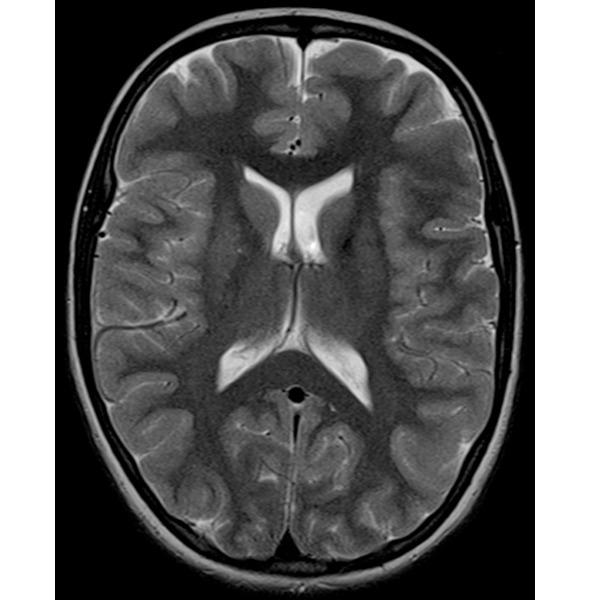

Помимо всего этого, у мозга есть еще одна потрясающая способность — способность сжиматься без какой-либо травмы вещества мозга, если в голове постепенно уменьшается полезный объем. На фото вы видите МРТ человека с нормотензивной гидроцефалией (стр.7), а рядом обычное МРТ (стр.6).

При нормотензивной гидроцефалии объем желудочков мозга увеличивается постепенно. Вы видите, насколько мало места в черепе осталось непосредственно для головного мозга, примерно в два раза меньше нормального объема. И вот этот человек с такими проблемами в голове ходил на работу, начал отмечать замедленность мышления, снижения скорости обработки информации, поэтому обратился к неврологу. Нейрохирурги выполнили ему операцию, после которой желудочки мозга стали нормального размера. И он вновь стал думать так же быстро и великолепно запоминать информацию. И за несколько месяцев сжатия в его мозге не погибли клетки, там не возникло участков некроза, видимых на МРТ. Представьте, если бы мы сдавили мышцы бедра или предплечья. Уже через несколько часов был бы некроз мышц, а здесь несколько месяцев — и без последствий. Таким образом, компенсаторная способность к уменьшению объема у мозга совершенно поражает воображение.